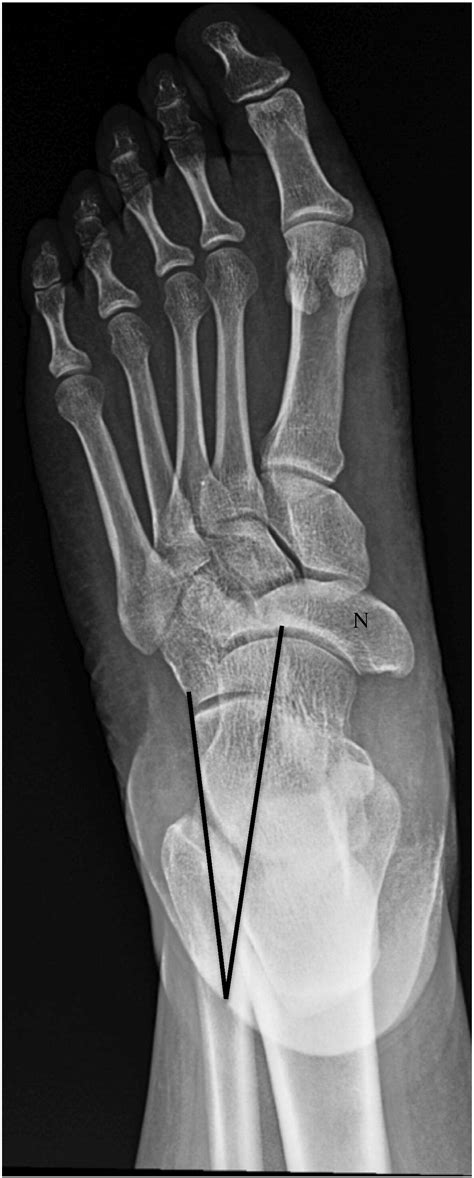

Mueller Weiss Syndrome is a rare degenerative disease of the navicular bone, a small, boat-shaped bone located in the midfoot. Unlike fractures caused by acute trauma, this syndrome occurs when the bone loses its blood supply, leading to fragmentation and collapse. While the exact cause remains somewhat elusive, it is frequently associated with mechanical stress, congenital anomalies, or systemic conditions that impede vascular flow.

Recognizing the symptoms of this condition early is critical for preventing severe structural damage. Because the navicular bone plays a vital role in supporting the medial longitudinal arch, its deterioration creates a domino effect across the foot.

X-ray (Weight-bearing) The primary tool to visualize the navicular bone's fragmentation and collapse.